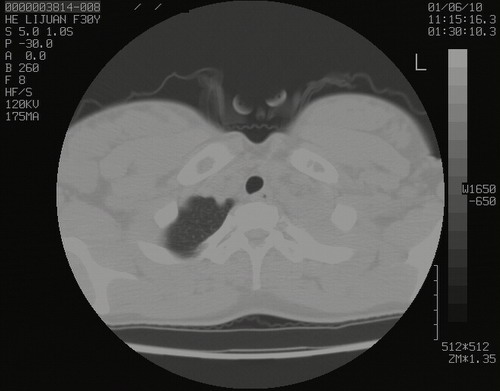

怀孕3个月时(2009-3至4月间),自述突感左侧前后胸疼痛1天,以前胸明显,随后偶感闷痛,余未见异

左肺尖脊柱旁沟肿块,境界清楚,边缘光滑,密度不均,内有多发点片状钙化,考虑良性肿瘤,骨软骨瘤或神经源性肿瘤可能,肺错构瘤不除外。

左后上纵隔见一类圆形肿块影,外侧边界清,密度不均匀,内可见点状钙化影,增强呈不均匀强化,考虑神经源性肿瘤可能。期待病理结果。